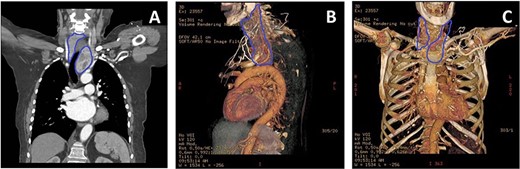

Intraoperatively, the hemi-thyroidectomy was initiated through a 7-cm cervical Kocher incision and cervical portion of the left hemi-thyroid was mobilized after division of middle thyroid vein and thyroid artery. Based on the pre-operative imaging, a right upper ‘J’ mini- sternotomy was performed through the third intercostal space. This exposed the inferior pole of retrosternal part of the goitre and also allowed clear access to the ascending aorta, aortic arch, right atrial appendage and inferior thyroid vessels facilitating their ligation (Fig. 3A). Finally the isthmus was divided and the left hemi-goitre removed (Fig. 3B and C). The cervical incision was then packed and full-dose heparin for CPB was given. Right atrial to ascending aorta bypass circuit was now easily established. Myocardial protection was achieved with (induction) antegrade and (maintenance) direct coronary ostial intermittent cold blood cardioplegia, and routine AVR performed through a transverse aortotomy using a Perimount MagnaEase Bioprosthesis using pledgeted 2-0 ticron sutures, anchoring the prosthesis in a supra-annular position. On completion, protamine was administered and wound closure completed following a final review of haemostasis.

(A) Intraoperative image showing hemi-goitre (blue outline) extending retrosternally [1], to ascending aorta [2] visualized via mini-sternotomy and Kocher incision. (B) Removed left hemi-goitre. (C) Post goitre removal [1], the extent of the tracheal deviation can be seen [2], through the cervical Kocher incision.